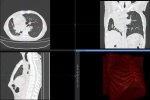

camphoto684387517.jpeg

camphoto1804928587.jpeg

Вот вам с ночной смены, немного посижу тут и спать

>>327477031

5 зон было?

Кросивое. Без воды хоть в брюхе и малом тазу?

Агась, ГМ-ШОП-ОГК-ОБП-ОМТ, в брюхе нихуя, а вот в легких кровяка была немношк, он с 15 метров яйцами пезднулся